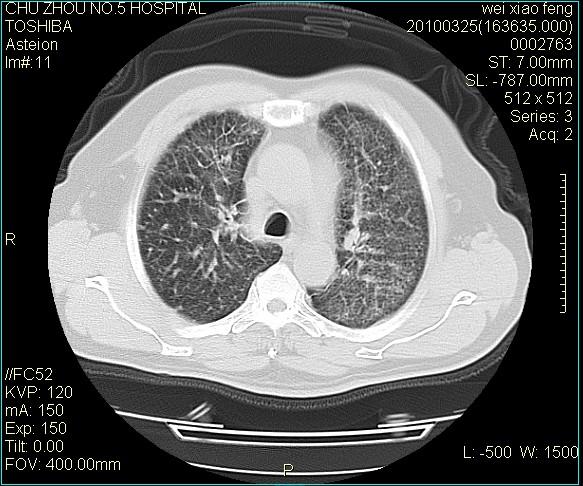

男,60岁,反复咳、痰、喘3月,加重3天。

双肺间质性改变。

考虑双肺血型潘散肺结核/

间质性肺炎伴间质纤维化!不排除伴有职业病!

急性血型潘散肺结核。

双肺间质纤维化,双肺血型潘散肺结核。

考虑间质性肺炎伴间质纤维化。

右肺中叶结节影为原发灶,考虑右肺中叶周围型肺癌并淋巴道转移

间质性肺炎